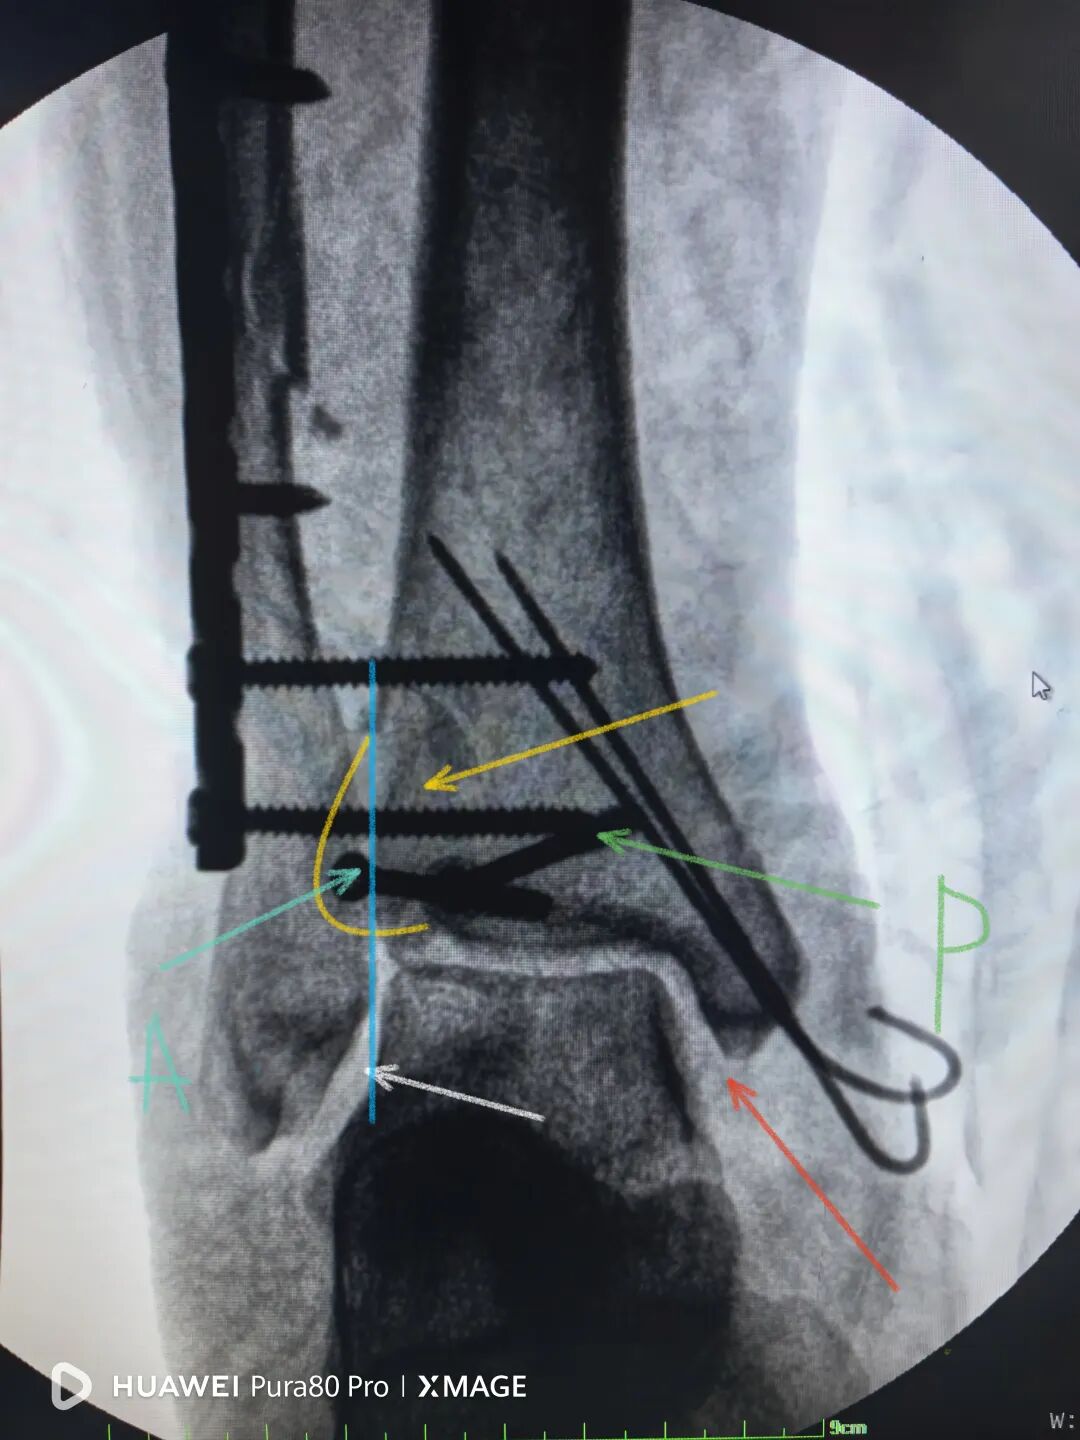

下胫腓关节复位良好

但前侧Chaput骨块

后侧volkmann骨块都移位